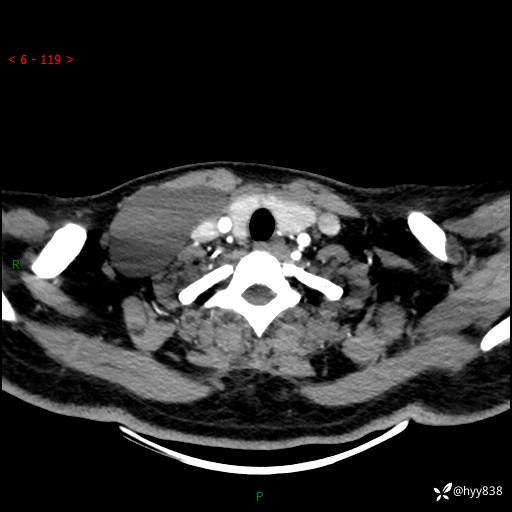

增强动脉期+静脉期